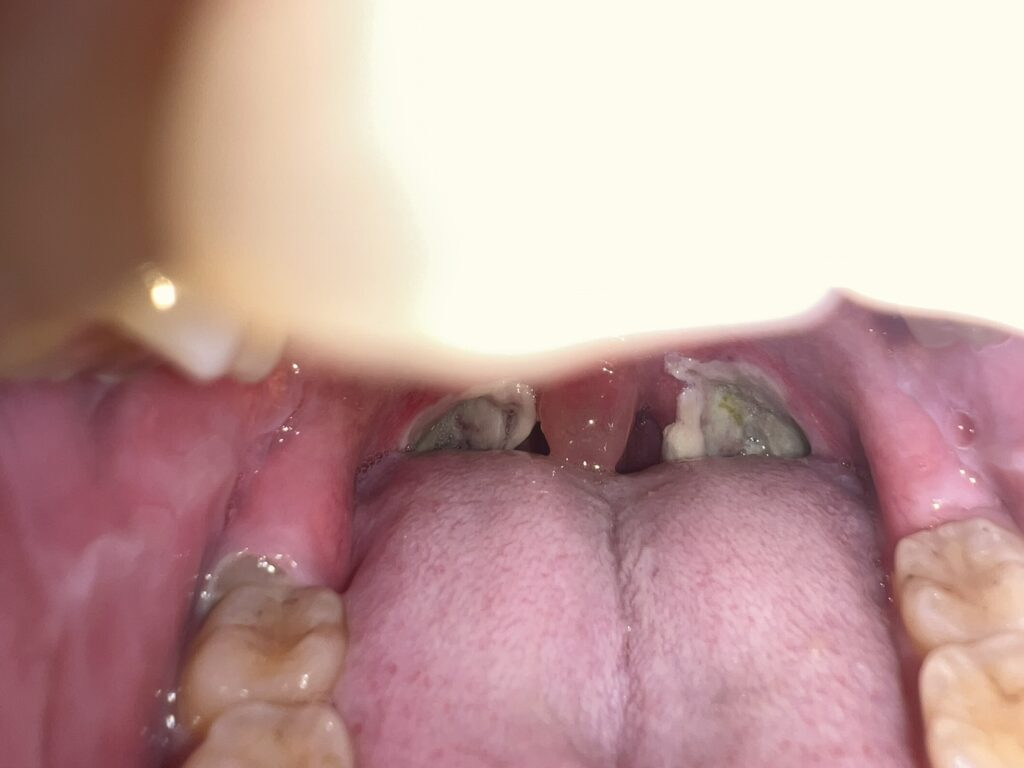

12月1日

12月2日(退院)

この白いのが全部剥がれ落ちて傷も治れば完璧と。術後4週間で完治とされるらしく12月16日までは一応気をつけてくださいとのことでした。